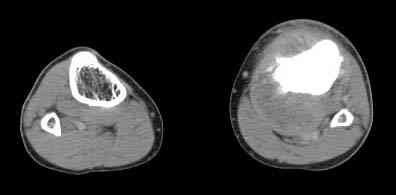

важаемые коллеги! Поступил больной 22 лет. Болен с января 2006 - появились боли в области верхнейтрети голени. При первичном осмотре в поликлинике был заподозрен первично-хронический остеомиелит - осмотрен гнойным хирургом - произведена биосия . Заключение - хондросаркома. Осмотрен онкологом - с учетом характера опухоли - химиотерапия, лучевое лечение не показано. Предложена либо ампутация, либо решение вопроса о возможности выполнения органосохраняющей операции. При обращении к нам произведена сцинтиграфия скелета - зоны гиперфиксации РФП: верхняя треть голени- 960%, нижняя треть бедра - 380%, Дистальный метафиз голени и затылочная область - 140%. В легких - метастазов нет. Произведена КТ (картинки в приложении). Учитывая абсолютную нестыковку рентгенологических и морфологических данных повторно биопсия. Выявлено, что первичная биопсия выполнялась из поверхностной параоссальной зоны - там локализованы хрящеподобные массы, далее очень плотная кость без хрящевых участков - биоптат взят фрезой с большим трудом. Морфологического заключения пока нет. Хотелось бы узнать Ваши варианты диагноза и соответственно тактику.

Не специалист по онко ортопедии, но по локализации (бедро, большеберцовая и плечевая кость), возрасть, в данный момент отсутствия метастаза и формация новой кости с мягкотканним вовлеченим, процесс больше напоминает остеосаркому большеберцовой кости.

Биопсия затрудняется из-за склероза, онко ортопеды пользуются для биопсии специальным набором режущих игл.